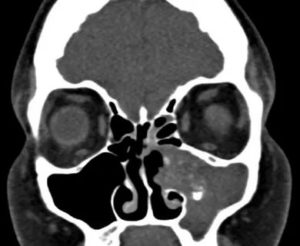

Надежный и информативный диагностический метод. Его эффективность обусловлена внешним видом мицетомы на поздней стадии. В отличие от полипов и раковых клеток, микоз имеет высокую плотность, сравнимую с металлом.

При выведении изображения на томограф, можно заметить объемную шарообразную массу с незначительными структурными изменениями. Плюс метода – полная безопасность для организма, быстрота проведения и возможность использования снимков.

и наиболее информативная методика обнаружения мицетомы — проведение КТ (компьютерная томография). Дело в том, что плотность мицелия аспергилл совпадает с плотностью металла, на получаемых томограммах хорошо виден очаг инфекции. Легко распознать мицелий, который окружён массами, рентгенологическая плотность которых снижена.

Рентгенологическая плотность мицетомы сравнима с плотностью металла. На снимке грибное тело отмечается как яркое пятно, которое окружают массы, менее плотные рентгенологически. Реже грибковый шар определяют при помощи МРТ.